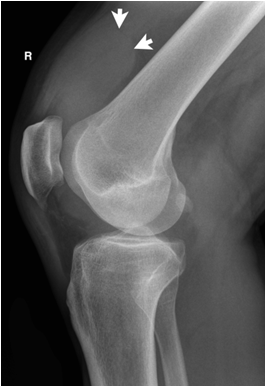

Soft tissue swelling may be discerned not only by the apparent increase in the soft tissue but also by the interruption of normal fat planes. If subcutaneous fat or fat between muscle planes is infiltrated by edema (water density), the fat plane will no longer be visible since it loses its sharp contrast with water density structures like tendons or muscle.

Fig. 6. Patient with knee trauma. Plain films reveal significant suprapatellar joint effusion (white arrows). A fracture is not seen. MR imaging reveals a torn anterior cruciate ligament (white arrow head).